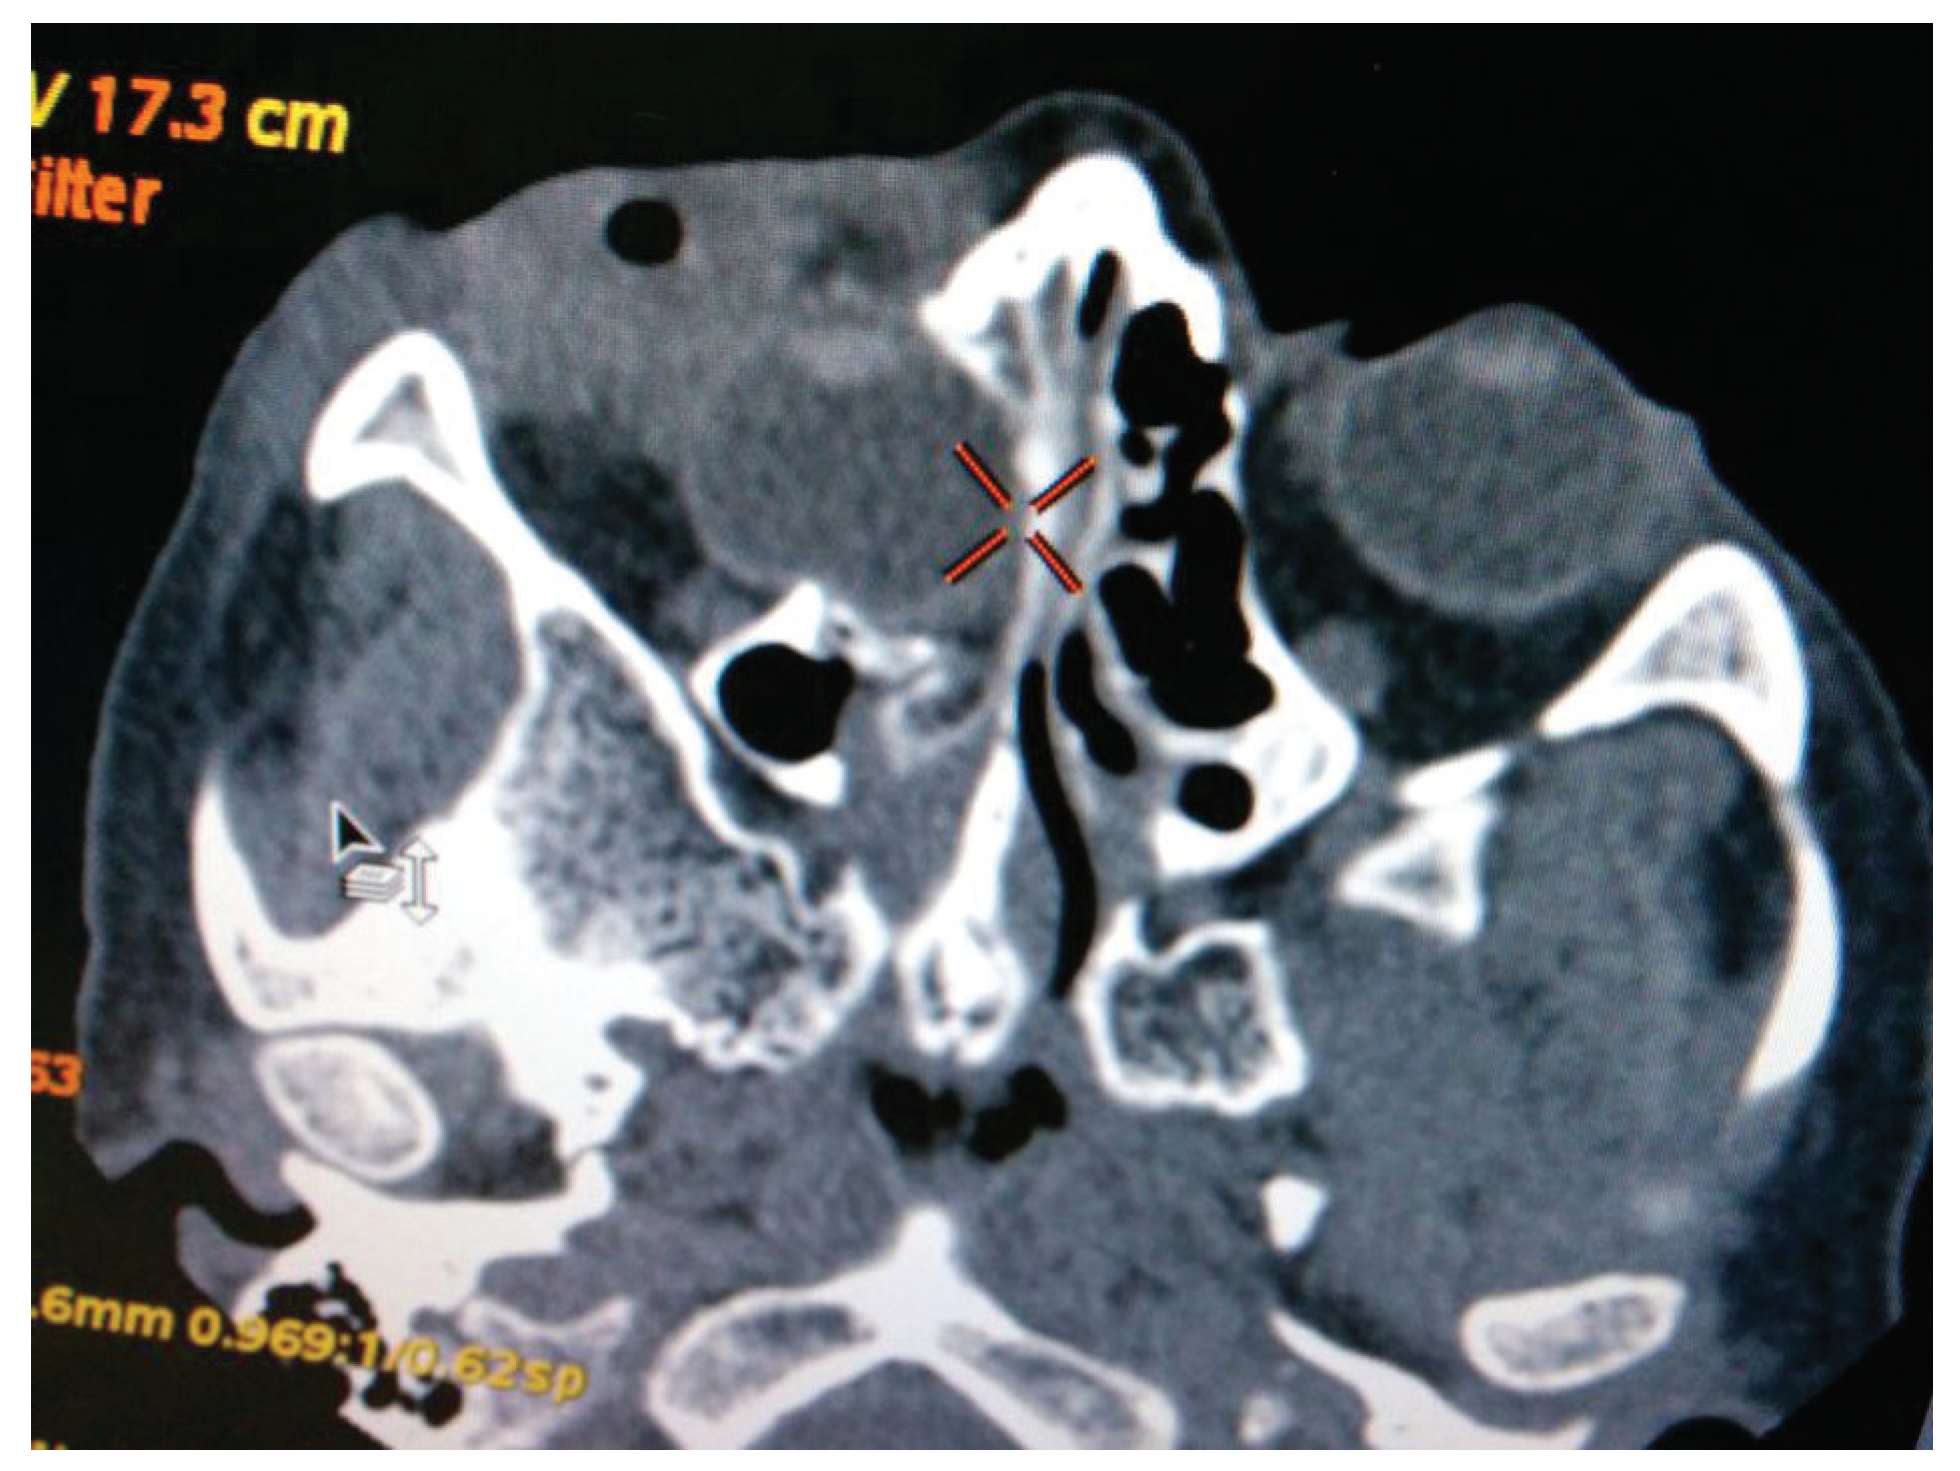

Diagnostic Assessment